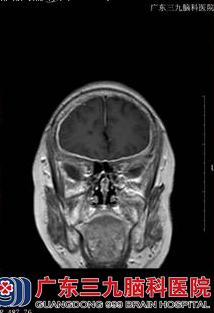

71岁的刘某本可在家安度晚年,坐享天伦之乐,可是,就在一年多前,她出现了右侧头部疼痛,阵发性枕部牵拉痛,持续数分钟至数小时不等,每天上午约11时出现剧烈疼痛,到相关医院进行眼眶CT示双侧眼球内斜位,头颅MRI+MRA示右侧额叶、基底多发性腔梗,右侧中后组筛窦、蝶窦,暂考虑炎症,由于刘某还出现了视力下降,在眼科医院眼球彩超室双侧玻璃体混浊(+)伴后脱位。脑脊液常规示白细胞17*106/L,脑脊液生化示蛋白0.87g/L,颅脑MR增强示双侧大脑及小脑幕脑膜增厚,右侧明显,考虑一个脑膜炎,给予相关治疗后,效果差,2014年10月,刘某左眼亦出现视力下降,到其他医院行头颅MRI+增强示弥漫性硬脑膜强化并右额颞部硬膜下小血肿,脑脊液常规示白细胞20*106/L,脑脊液生化示蛋白1.714g/L,再接受相关治疗后,刘某仍感不适,遂到广东三九脑科医院进一步治疗。

收治入院后,完善相关检查发现:患者意识清楚,懒言少语,言语不清,记忆力、计算力、定向力等认知功能下降,MMSE13分(存在认知功能障碍),右侧眼裂小,右眼失明,右侧瞳孔扩大,直接对光反射迟钝;左侧瞳孔正常,直接对光反射稍迟钝,余脑神经(-),双下肢肌力五级弱,肌张力正常,双侧腱反射(++),左侧Babinski征、Chaddock征均(+),颈部绵软,Kernig征、Brudzinski征均(-),双侧指鼻试验、快复轮替动作及跟膝胫试验均完成。故初步诊断为:1、头痛查因:硬脑膜炎(特发性肥厚性)?2、脑梗死?3、硬膜下血肿(恢复期)?神经内二科王展航主任在详细了解病人病情后,制定了详细的治疗方案,给予病人改善脑循环、神经营养、激素、康复治疗等加强对症支持治疗。

【头颅MRI结果】: